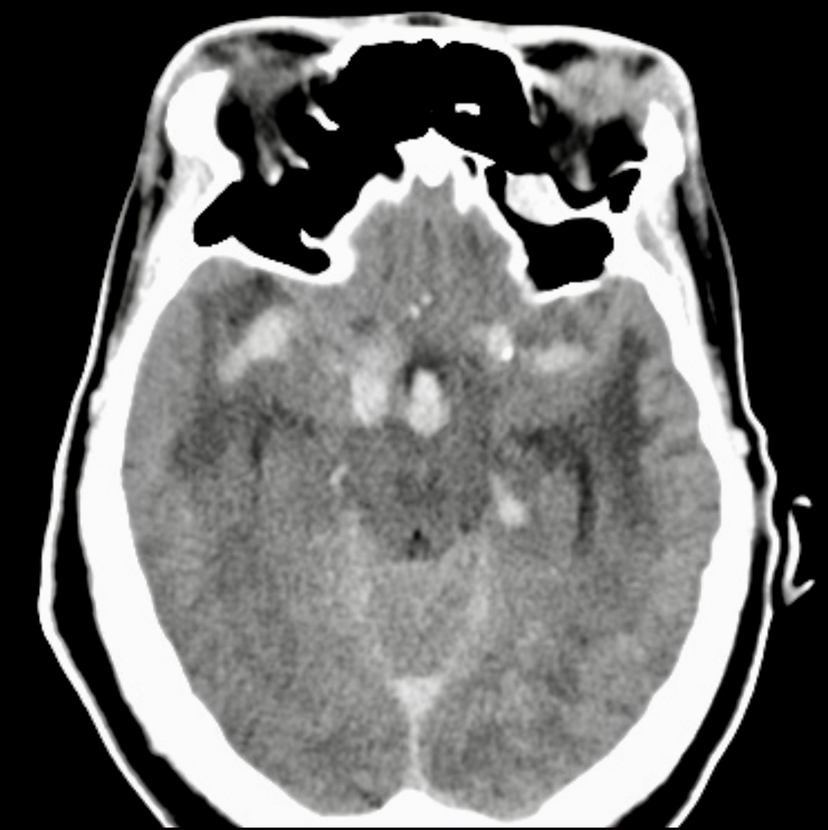

女性,50岁。自发性蛛网膜下腔出血并昏迷3天入院。病史:垂体生长激素腺瘤外院术后复发。查体:肢端肥大面容,昏迷,hunt-hess分级4级。GH19,明显高于正常值。行头颅CT检查显示蛛网膜下腔出血,蝶鞍扩大。

DSA检查发现颅内共12枚形态各异的动脉瘤,其中基底动脉瘤形态不规则,大小约15*13mm,瘤颈部累及双侧大脑后动脉P1段,双侧后交通动脉和前交通动脉不显示,瘤顶部有子囊发出。